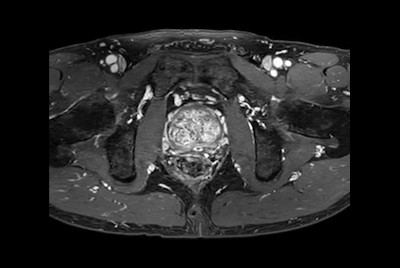

Fast Prostate imaging with SmartSpeed Precise